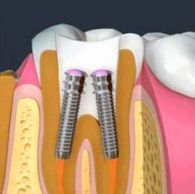

The final stage of the root canal is restoring your tooth. Because the tooth typically has a large filling or is weakened from extensive decay, it needs to be protected from future damage and returned to normal function. This is usually done by placing a crown — a realistic-looking artificial tooth. A crown is made of gold, porcelain or porcelain fused to metal. It can be tinted to match the exact color of your other teeth. Sometimes, a metal post must first be inserted in the tooth for structural support and to keep the crown in place. Ask your dentist or endodontist about other restoration options.

A post and core is a dental restoration used to sufficiently build-up tooth structure for future restoration i.e crown when there is not enough tooth structure to properly retain the crown. post is placed within the body of the root of a tooth that has already treated with root canal treatment.